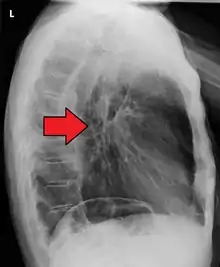

Additional testing is needed to assess how much the cancer has spread (see § Staging, below). Computed tomography (CT) of the chest, abdomen and pelvis can evaluate whether the cancer has spread to adjacent tissues or distant organs (especially liver and lymph nodes). The sensitivity of a CT scan is limited by its ability to detect masses (e.g. enlarged lymph nodes or involved organs) generally larger than 1 cm.[43][44] Positron emission tomography is also used to estimate the extent of the disease and is regarded as more precise than CT alone.[45] PET/MR as a novel modality has shown promising results in preoperative staging with fair feasibility and good correlation in comparison to PET/CT. It can enhance tissue differentiation with lowering the radiation dose to the patient.[46] Esophageal endoscopic ultrasound can provide staging information regarding the level of tumor invasion, and possible spread to regional lymph nodes.

Contrast CT scan showing an esophageal tumor (axial view)

Contrast CT scan showing an esophageal tumor (coronal view)